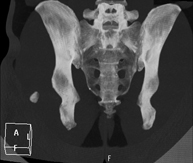

Exploració radiològica que mitjançant un sistema de raigs X i detectors que giren al voltant del pacient i que reconstrueixen les imatges per ordinador (TC Multidetector), permet l'estudi detallat dels ossos, els músculs i les articulacions de la mà i el canell. - TC de la pelvis òssia

Exploració radiològica que mitjançant un sistema de raigs X i detectors que giren al voltant del pacient i que reconstrueixen les imatges per ordinador (TC Multidetector), permet l'estudi detallat dels ossos, els músculs i les articulacions de la pelvis. - TC de malucs

Exploració radiològica que mitjançant un sistema de raigs X i detectors que giren al voltant del pacient i que reconstrueixen les imatges per ordinador (TC Multidetector), permet l'estudi detallat dels ossos, els músculs i les articulacions del maluc. - TC de sacroilíaques

Exploració radiològica que mitjançant un sistema de raigs X i detectors que giren al voltant del pacient i que reconstrueixen les imatges per ordinador (TC Multidetector), permet l'estudi detallat de les articulacions sacroilíaques i descartar malalties inflamatòries, traumàtiques o degeneratives. - TC de genoll